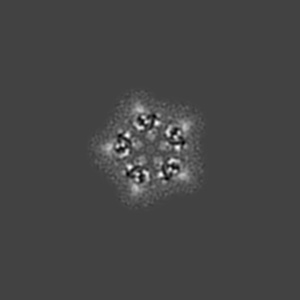

Cryo-EM structure of 5HT3A receptor in presence of Ondansetron

Sample: Serotonin receptor

High-resolution structures of multiple 5-HT 3A R-setron complexes reveal a novel mechanism of competitive inhibition.